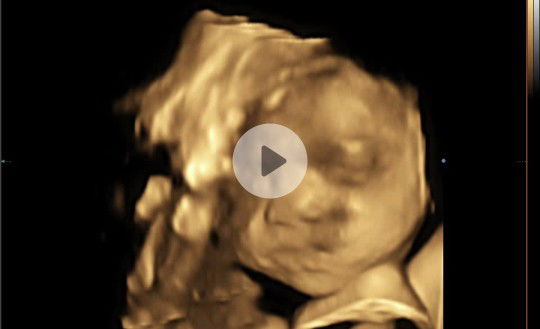

ito po yung link ng 4D ultrasound ni baby.. https://youtu.be/EXpNQjSOvIM P3,000 po lahat, nakainstall sa CD ang videos and pics. Para saken worth it po, nagkaron po ako ng peace of mind after makita na healthy si baby inside my tummy.. Minsan kasi kung anu-ano naiisip natin about kay baby, na baka may abnormalities, cleftlip, etc. Pero after maultrasound nawala lahat ng takot ko, at mas lalo pa ako naexcite makita si baby sa personal. God bless to all moms.